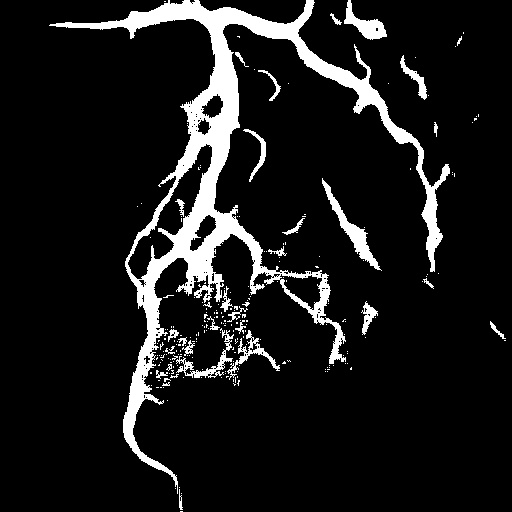

4.1 XACV Dataset

We collect 111 complete records of coronary artery X-ray videos, encompassing the injection, flow through the blood vessels around the heart, and dissipation of the contrast agent. Subsequently, we establish the XACV (X-ray Angiography Coronary Video) dataset. Each video consists of varying numbers of high-resolution coronary artery X-ray images. We invite experienced radiologists to annotate the vascular regions, focusing on one or two frames where the contrast agent is most prominent in each video. The XCAD dataset contains only a single image, and the CADICA video dataset does not provide corresponding ground truth. Therefore, in the following experiments, we conduct all the analyses on our collected XACV dataset and the corresponding GT for each sequence. In Figure 5, we show that compared to other publicly available datasets, XCAD [33] and CADICA [19], our dataset exhibits finer annotations in the vascular regions, providing an advantage for future related tasks. The development and use of our dataset have been approved by our institution’s IRB.